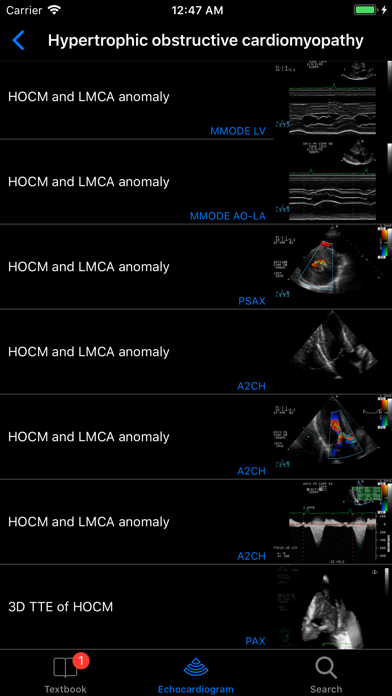

- Main chapters include Basic Principles, Valvular Heart Diseases, Cardiac Masses and Infective Endocarditis, Pulmonary Embolism and the Right Ventricle Function, Cardiomyopathies and Myocarditis, Diseases of the Aorta, Diseases of Pericardium, Congenital Heart Diseases in the Adult, and Cases